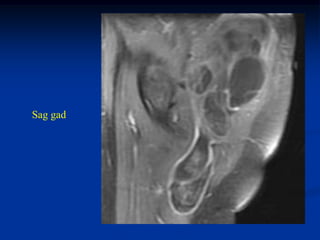

Case #1184.1              Lipoma               CT scan

51 year old male with soft painless mass in buttocks for 5 yrs

Axial T-1     T-2

Gad

Cor T-1         T-2

Sag gad

Case #1184.1 Lipoma CT scan 51 year old male with soft painless mass in buttocks for 5 yrs

• 50.

Axial T-1 T-2 Gad

• 51.

Cor T-1 T-2 Gad

• 52.

• 53.